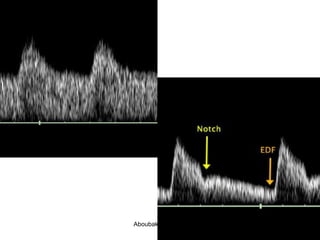

Normal

Absent

Reversed

UAD: Normal

UAD: notch,

decreased diastolic

flow

UAD: Normal UAD: notch, decreaseddiastolic flow Aboubakr Elnashar